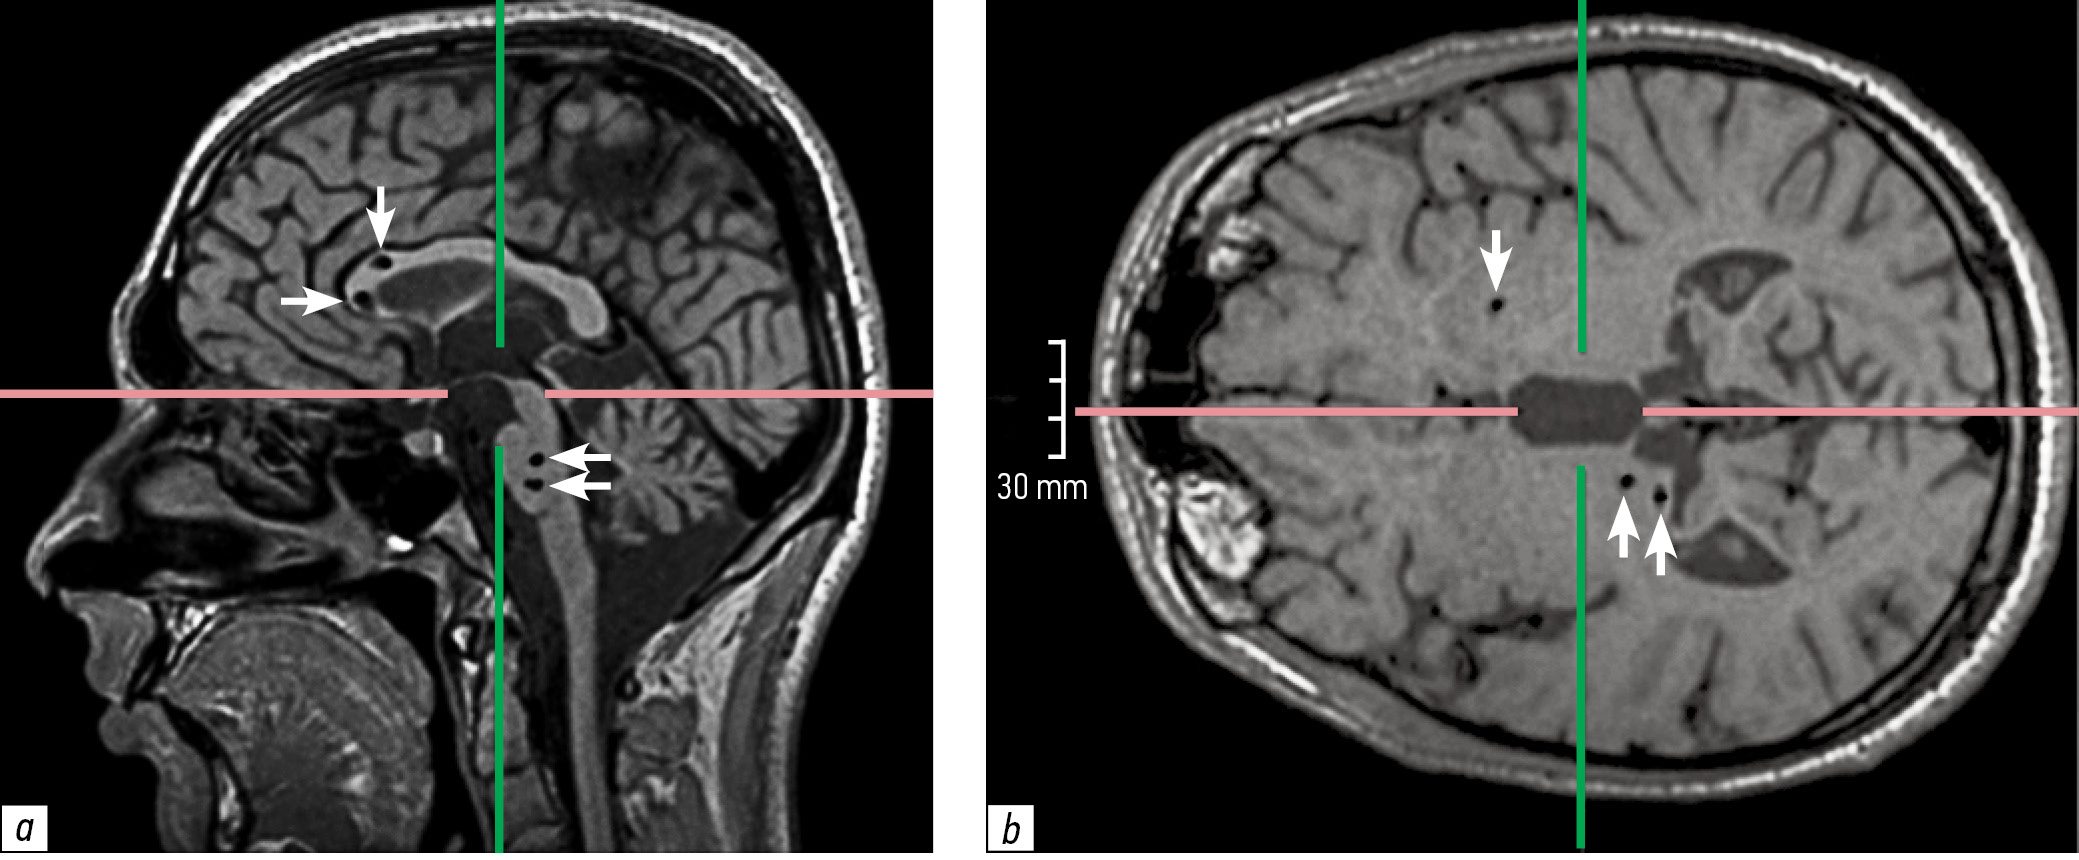

В августе 2023 г. пациент был госпитализирован в профильное отделение Городской клинической больницы № 52. Результаты дообследования: лабораторно отмечались повышение уровня СРБ до 10 мг/л (норма 0–5), незначительное снижение уровней иммуноглобулина (Ig) A до 1,2 г/л (норма — от 2,1), нейтрофилов до 1,4 × 109; остальные показатели, в том числе общего анализа крови и мочи, биохимического анализа крови, антинуклеарного фактора, антител к кардиолипину, гликопротеину, С3, С4, IgG, IgM, CD4+, CD8+, CD19+, CD3−CD56+CD16+, находились в пределах нормальных значений. Дополнительно выполнено расширенное иммунофенотипирование В-лимфоцитов: созревание В-клеток не нарушено, содержание субпопуляции переключенных В-клеток памяти достаточное — 12 % от общего содержания В-клеток. По данным инструментального обследования (компьютерная томография органов грудной клетки, брюшной полости, малого таза с внутривенным контрастированием, ультразвуковое исследование периферических лимфатических узлов, щитовидной железы) клинически значимых отклонений не выявлено. При МРТ головного мозга выявлены единичные мелкие участки в мозолистом теле и бассейне средней мозговой артерии справа, многочисленные очаги кистозно-глиозных изменений суб- и супратенториальной локализации, гипоплазия червя мозжечка и стволовых структур, умеренная внутренняя гидроцефалия (рис. 1).

Рис. 1. Магнитно-резонансная томограмма головного мозга в сагиттальной (a) и горизонтальной (b) плоскостях. Суб- и супратенториально определяются множественные очаги кистозно-рубцовых изменений на границе колена и клюва мозолистого тела, в структуре колена мозолистого тела, правого таламуса, Варолиевого моста (стрелки). Червь мозжечка и стволовые структуры гипоплазированы.

Fig. 1. Magnetic resonance imaging of the brain. Sagittal (a) and horizontal (b) plane. Multiple foci of cystic and scarring changes are visualized sub- and supratentorially at the border of the genu and rostrum of the corpus callosum, in the internal structures of the genu of corpus callosum, internal structures of the right thalamus, internal structures of the pons (arrows). Vermis and brainstem structures are hypoplastic.